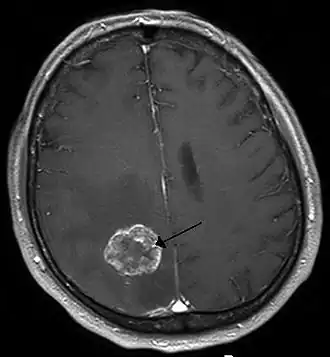

Tumor cerebral

Metástasis en el hemisferio cerebral, procedente de un cáncer de pulmón. | ||

El tumor cerebral es un crecimiento descontrolado de células derivadas de componentes cerebrales (tumores primarios) o de células tumorales localizadas en otras áreas del organismo (metástasis).[1]

Los tumores pueden ser benignos o malignos, dependiendo de la rapidez de su crecimiento y de si logran resecarse o curarse mediante el tratamiento neuroquirúrgico. Las metástasis hacia el sistema nervioso central provienen, en orden de frecuencia, del pulmón, mama, piel (melanoma), riñón y gastrointestinal y tienden a crecer entre la unión de la corteza y la sustancia blanca.[cita requerida]

Tumores secundarios (metástasis)

Las células cancerígenas de un sitio primario pueden viajar hasta el cerebro a través del sistema circulatorio, a través de la vía linfática y del líquido cefalorraquídeo. La forma más común es la circulatoria.

El cerebro es el sitio de preferencia de metástasis del melanoma y del cáncer de las células pequeñas de pulmón. En el varón, las metástasis provienen principalmente del pulmón, del colon y del riñón. En la mujer, los casos más frecuentes son el cáncer de mama, de pulmón, de colon y el melanoma.[27] Las metástasis espinales ocurren en el 5 por ciento de los pacientes con cáncer, más frecuentemente en el cáncer de mama, de próstata y el mieloma múltiple.

El diagnóstico se realiza mediante exámenes imagenológicos como la TAC o la resonancia magnética (RM), las cuales permiten conocer la localización y el tamaño del tumor y además sugerir la naturaleza del mismo, pero es la biopsia la que indica el tipo exacto de tumor.